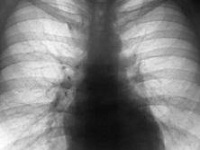

特发性肺纤维化(idiopathic pulmonary fibrosis,IPF)系指IIP中病理表现为寻常型间质性肺炎的一种类型,在llP中最常见,占47%-71%。病变局限于...[详细]

高分辨CT(HRCT)的诊断特发性肺纤维化

特发性肺纤维化是指原因不明的以普通性间质性肺炎为特征性病理改变的一种慢性炎症性间质性肺病,主要表现为弥漫性肺泡炎、肺泡单位结构紊乱和肺纤维化。云南省肿瘤医院胸外科李高峰本病的早期...[详细]